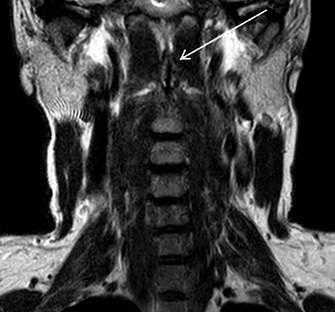

На мр-томограммах выявлялась расщелина (незаращение) передней дужки атланта, определялись особенности анатомического строения и особенности контуров передней дужки атланта в каждой из стандартных проекций (рис. 2).

Рис. 2. Коронарный и сагиттальный срезы Т2ВИ (стрелкой указаны поверхности расщепленной передней дужки)